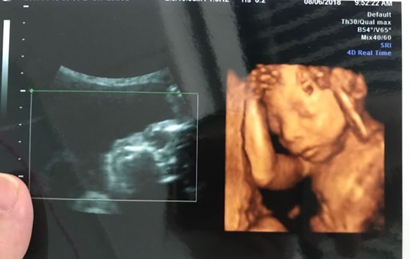

四维超声是一种比较先进的检查方式,也是实时的动态三维超声,一般来说通过四维超声来辨别宝宝性别是比较准确的,四维单子上出现了四个字的就是怀了男宝...

这四个字就是肾盂分离,为什么说单子上有这四个字是怀了男宝呢,其实这和胎儿在母亲体内的行为有关,双侧肾盂分离提示是男宝的概率占到80%到90%,这也是因为男宝宝独特的生理性结构特征容易出现尿潴留的情况,也就是说男宝宝在妈妈体内是会憋尿的,从而导致肾盂被充盈而出现变大的现象,只要肾盂分离不超过10mm那就是正常的。

一:在彩超单上会印,顶头最右边有两行字,是英文字母和数字组成的,第一行是日期,第二行是时间,如果第一行是M开头,那就是male男,如果是F开头就是female女,第二行打头的T是时间的意思。

二:彩超单上通常有“双侧肾盂分离”,那90%是男孩;如果是“双侧肾盂未见明显分离”,那95%是女孩。

三:彩超单上很小英文字母Qual high 1是女孩,2是男孩。

四:通过四维彩超图看清胎儿性别,在六个月以后照四维彩超,只要宝宝的姿势是正面不是给个背影什么的,是男是女一看就知道。不过因为国家明文规定不能查胎儿性别,所以医生不会把能明显看出性别的一面照给妈妈看。